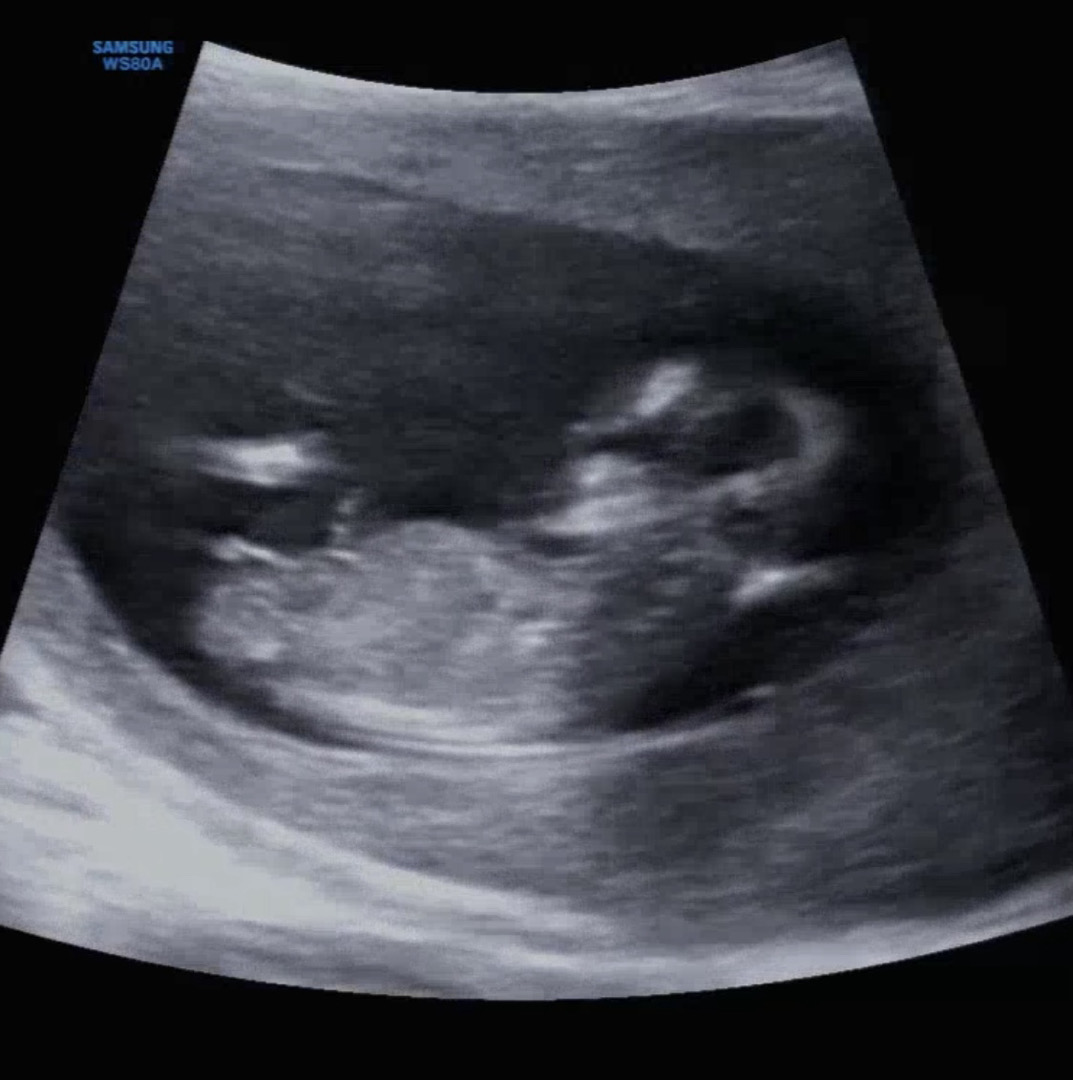

12주 각도법 !!

각도법 부탁드립니다 아무리 봐도 잘 모르겠어요ㅠㅠㅠ